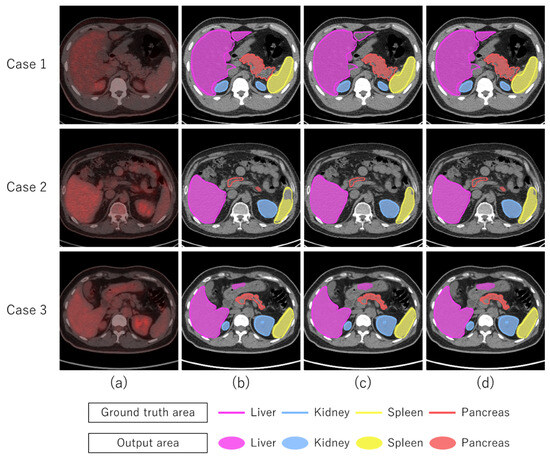

1.1. Related Works

3. Results

4. Discussion